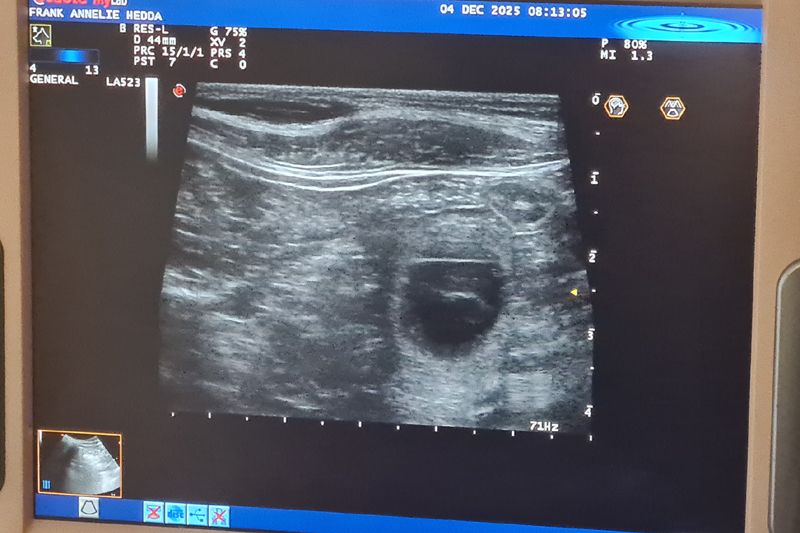

Ultraljud på måndag

På måndag gör vi ultraljud för att se om Fanny har valpar i magen. Håll tummarna!

Inga valpar....

Fennel är tyvärr inte dräktig. Vi har tyvärr haft otur igen med fryst sperma. Det är så trist för det finns så många fantastiska hanar där ute i världen

som jag så gärna vill ha i min avel. Men vi ger inte upp så lätt!